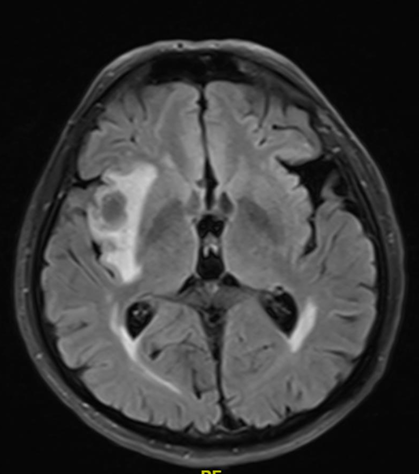

患者为69岁男性,吸烟史长达55包年,患有慢性阻塞性肺疾病(COPD),因背痛2月余入院。2021年12月,胸部CT和脑部MRI检查发现右侧上叶占位性病变,大小为68×66mm,并伴有右侧额颞部低密度病灶。2022年1月,PET-CT显示右侧上叶病灶增大至84×50mm,SUVmax为15.7,纵隔淋巴结(右侧气管旁、主动脉肺动脉、血管周围、气管旁)受累,SUVmax为3.15,右侧肾上腺转移灶大小为33×40mm,SUVmax为11.1。